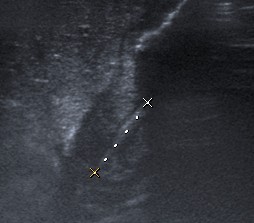

Se consideran diagnósticas un grosor de la capa muscular de 3 mm y una longitud del canal pilórico elongado de 14 mm. En general, ninguna de las medidas es tan importante, porque si el músculo está patológicamente engrosado, el canal estará elongado y fijo por el espasmo sin que se produzca una relajación del píloro para el paso de contenido desde el estómago al duodeno.